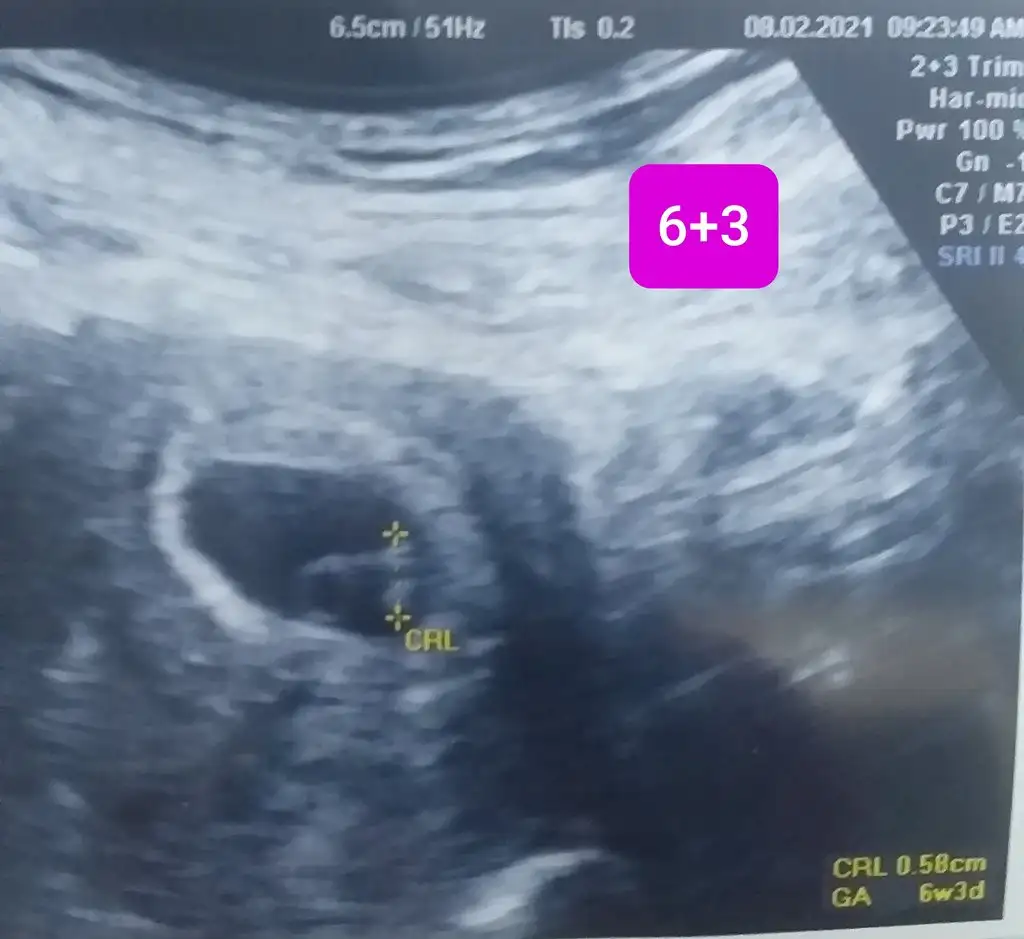

6+6 haftalık karından ultrason bana da yorum yapabilir misiniz?